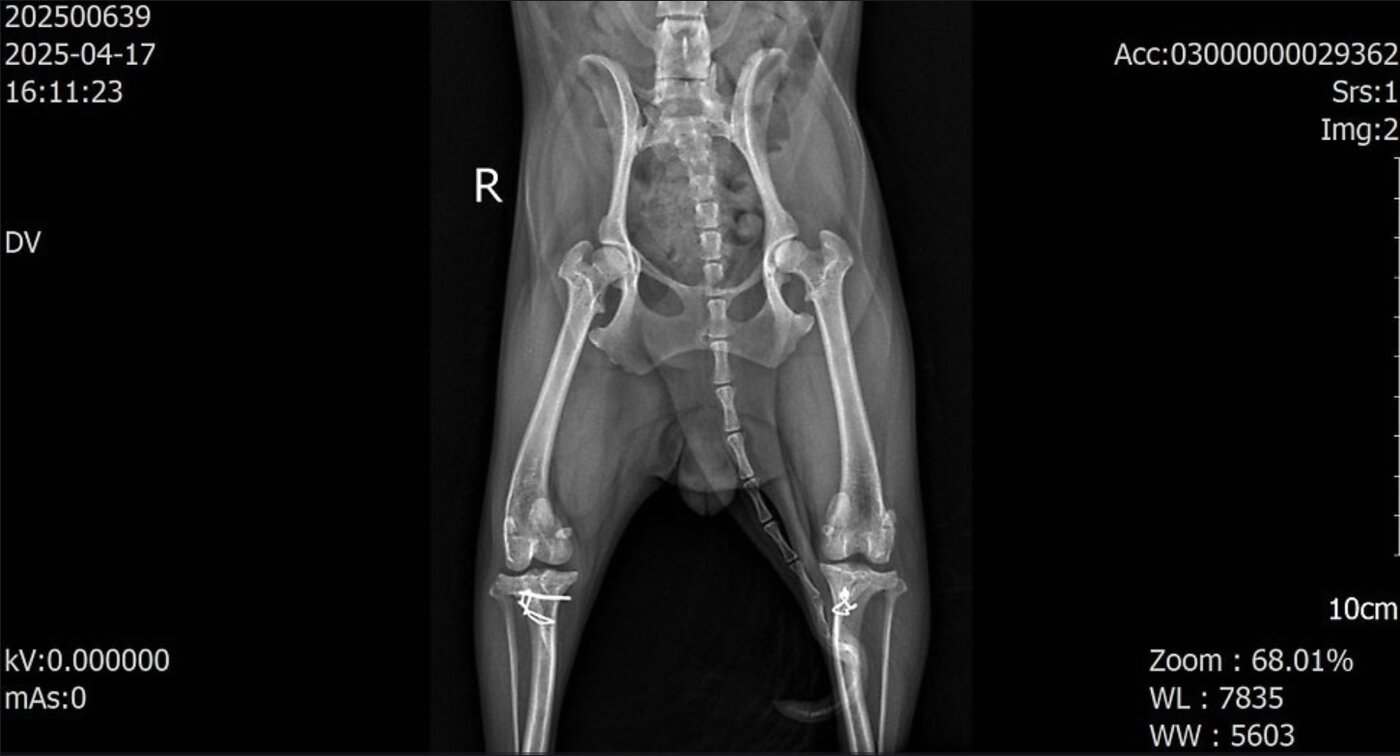

본문 이미지 - 슬개골탈구 수술을 받았지만 재탈구와 활차구 변형, 근육량 감소가 동반된 반려견의 엑스레이 사진(월드펫동물메디컬센터 제공) ⓒ 뉴스1

슬개골탈구 수술을 받았지만 재탈구와 활차구 변형, 근육량 감소가 동반된 반려견의 엑스레이 사진(월드펫동물메디컬센터 제공) ⓒ 뉴스1